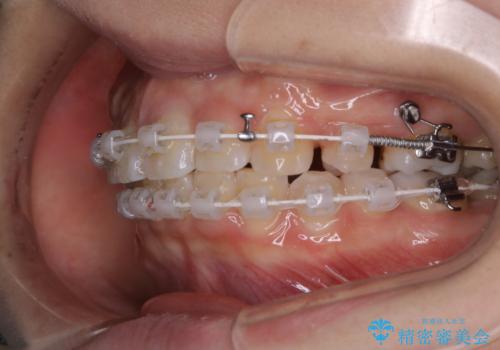

- 矯正装置

- 審美装置(ワイヤー)

- 前歯のがたつきが気になるとご相談にいらした方です。当初は前歯の部分矯正をご希望されていましたが、全体的に整えることで審美的、機能的な歯並びとなりました。

当初は上顎前歯のみの部分矯正をご希望されていましたが、部分的に前歯のみを並べると出っ歯感がつよくなり、食事もしづらくなる可能性をお伝えしました。全顎的な矯正治療により、審美的、機能的な歯並びとなりました。